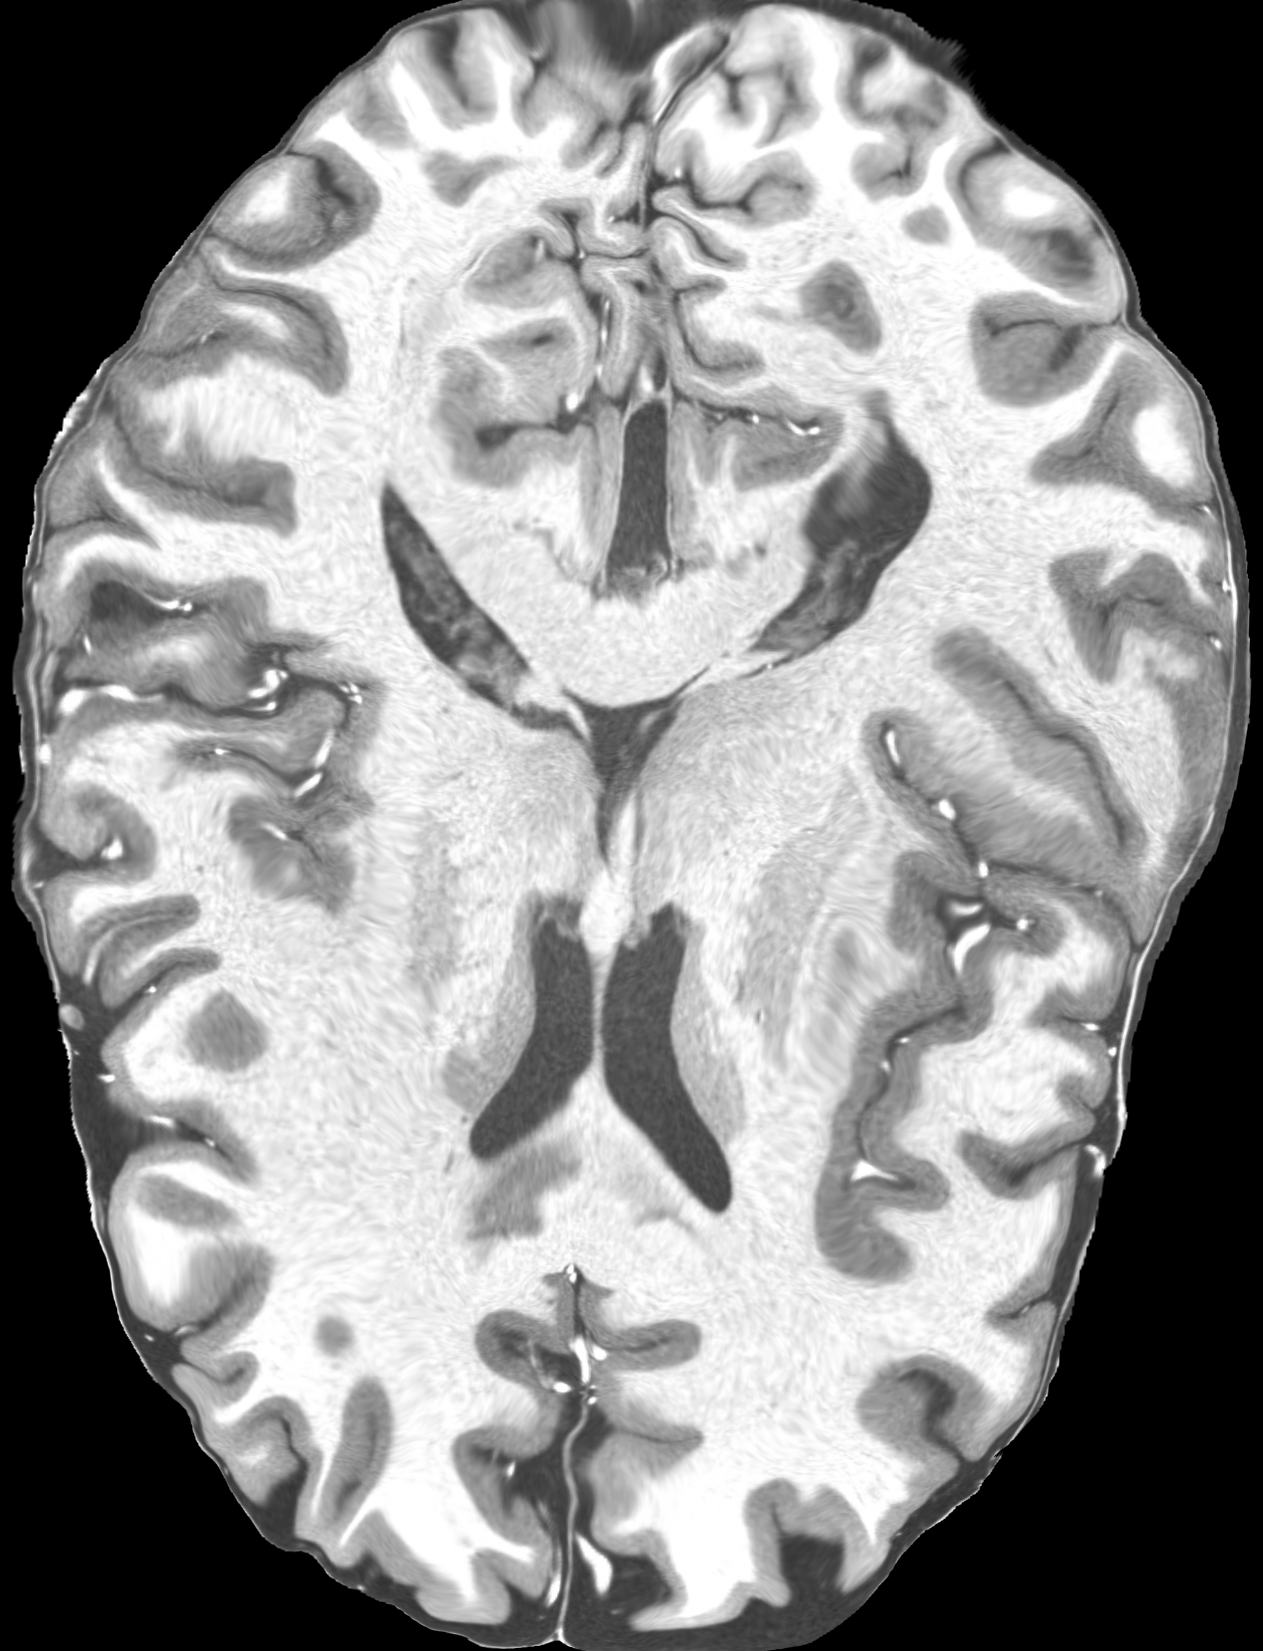

4.2 Registration to a 100 micron ex-vivo brain MRI volume

To showcase the efficacy of our method on real large scale images, we register a 250 in-vivo MRI image (Lüsebrink et al., 2017) to a 100 ex-vivo FLASH human brain volume (Edlow et al., 2019). This represents an inverse problem with more than 11.2B optimizable parameters (compared to 20M for clinical datasets), or 44.8GB of GPU memory. The entire problem does not fit on most GPUs, necessitating distributed multimodal registration. We optimize a composite transform - affine followed by a diffeomorphic mapping; details can be found in Section E.1. Multimodal deformable registration took 58 seconds on 8 NVIDIA A6000 GPUs, which is unprecedented at this resolution. Fig. 6 shows qualitative results, highlighting the ability to register highly detailed structures such as cerebellar white matter; these structures are not visible at macroscopic scales. The resultant advantages of performing registration at this scale can allow researchers to characterize the neuroanatomy at microscopic resolutions and allow morphometric analysis of cortical layers and subcortical nuclei among other structures.